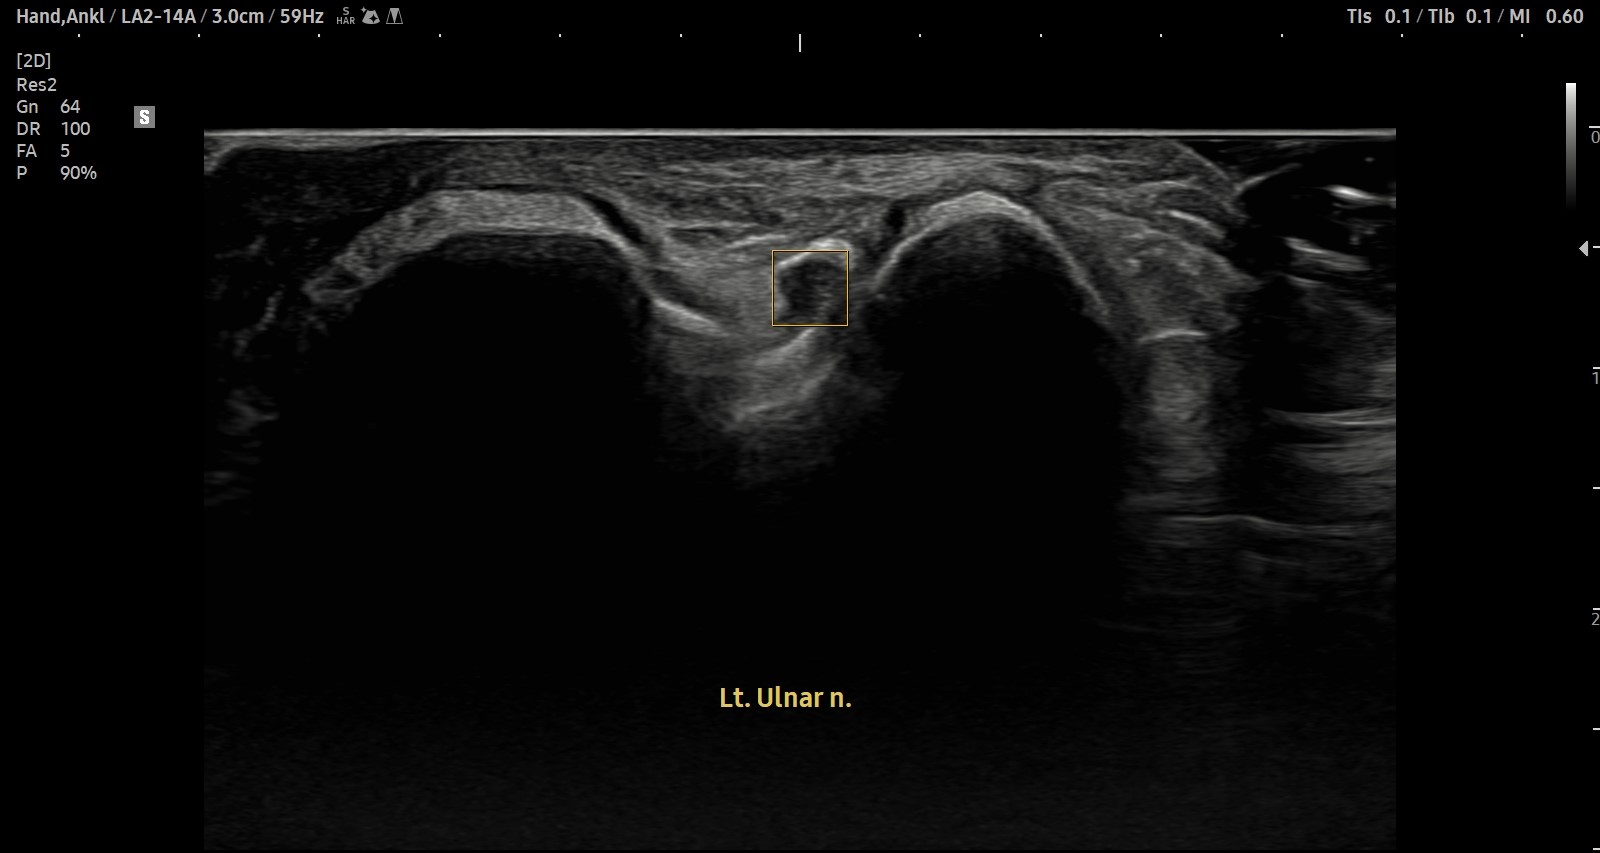

- 치료기간 : 25 . 9 . 27 ~ 25 . 11 . 19

- 치료횟수 : 12 회